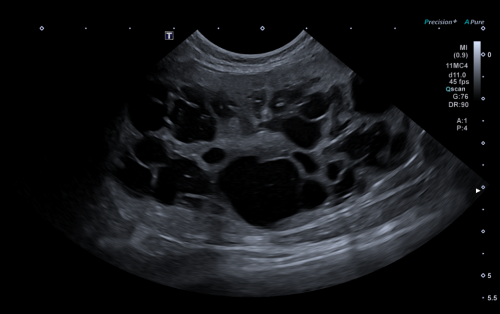

• Exposé théorique : sémiologie échographique, signes à rechercher et interprétation des principales lésions urinaires et génitales.

• Mise en pratique à partir de vidéos de cas cliniques pathologiques de l’appareil urinaire :

• Identification des lésions

• Description avec la terminologie adaptée

• Synthèse des anomalies observées

• Élaboration du diagnostic différentiel